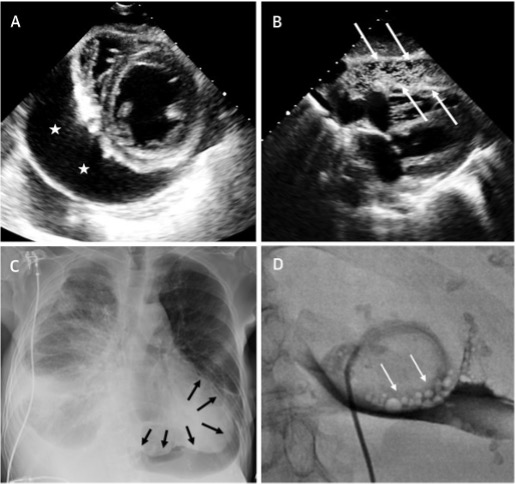

Pneumopericardium develops when a direct communication between pleura and pericardium forms, and air is introduced during the aspiration procedure, or when there is a leak in the drainage system. It occurs in about 1.5% of patients undergoing pericardiocentesis.